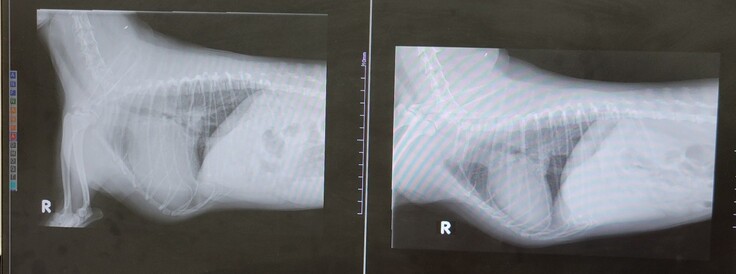

左が昨日の状態です。心臓も大きく、靄がかかっております。

昨日、23日の手術前の検査ということで、午前中に病院へいったところ、残念ながら肺水腫が再発しており、もう手術は待ったなし、という状況となりました。

肺水腫はあるものの、その他術前検査の結果自体は良好であったため、23日に正式に手術確定、ということで、あとはそこへ向かうのみ・・・だったのですが、今朝方にかけて、容体が悪化しました。

ぷらむは肺水腫3回目となり、繰り返すごとに肺の機能が低下するので、治りも悪くなります。